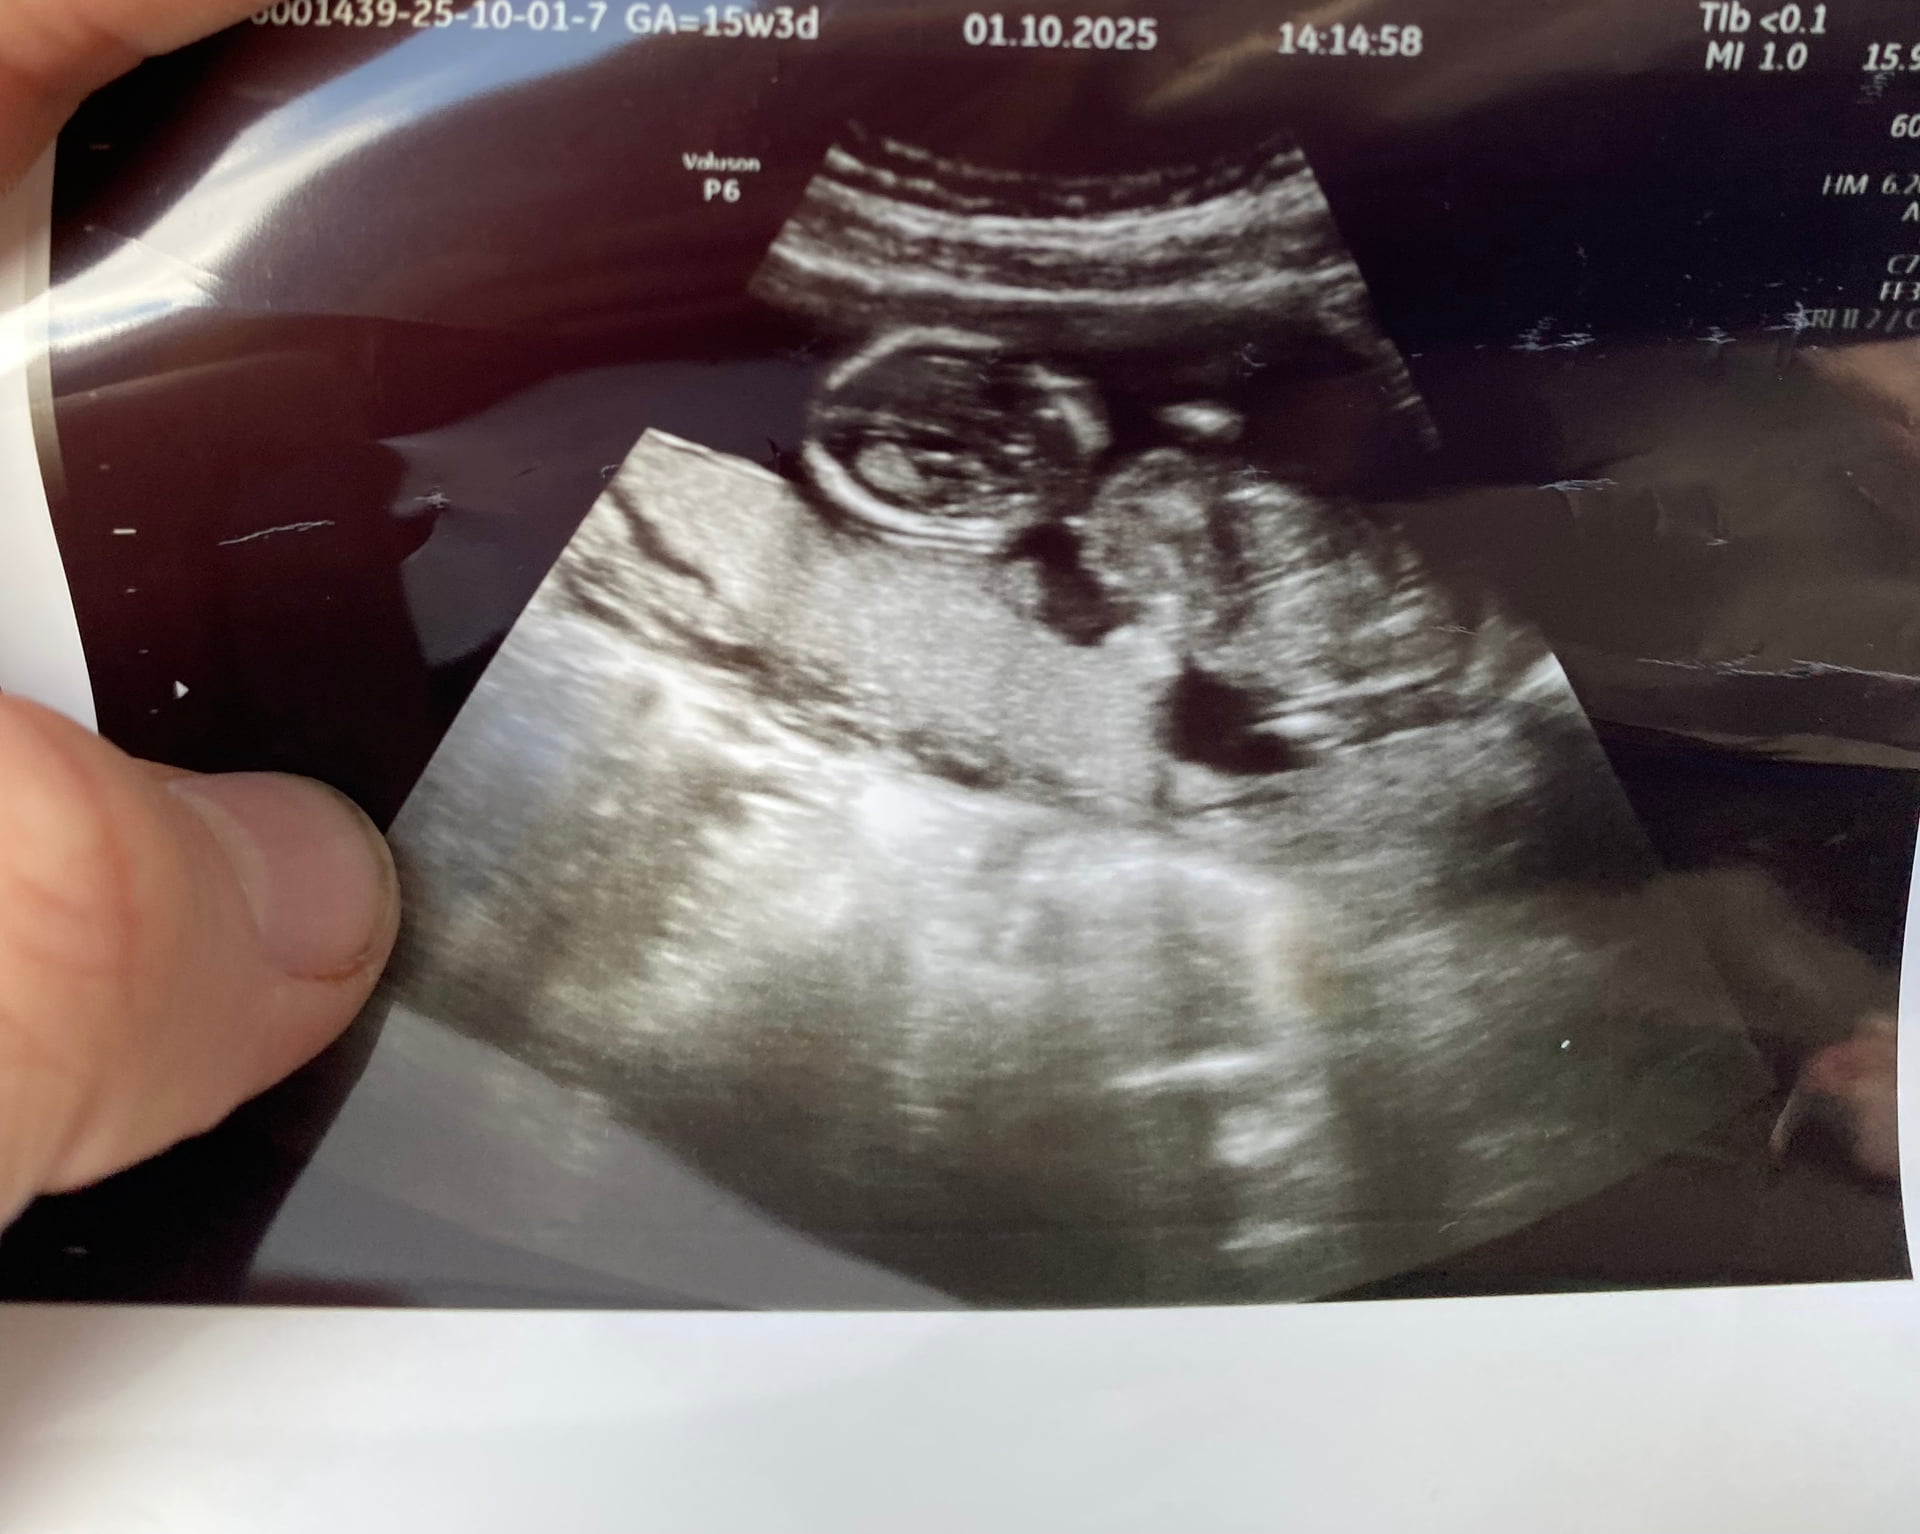

Sizce ney ![]()

![]()

Kese sekli gozukmuyor ki yakından kafa gozukuyor sadece. Uzaktan var mi